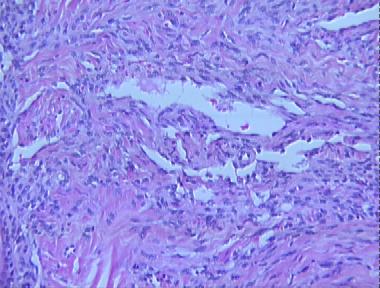

Kaposi's sarcoma, plaque stage

Kaposi's sarcoma, plaque stageBuy A Systematic Approach to Dermatopathology on Amazon.com

Histologic Features